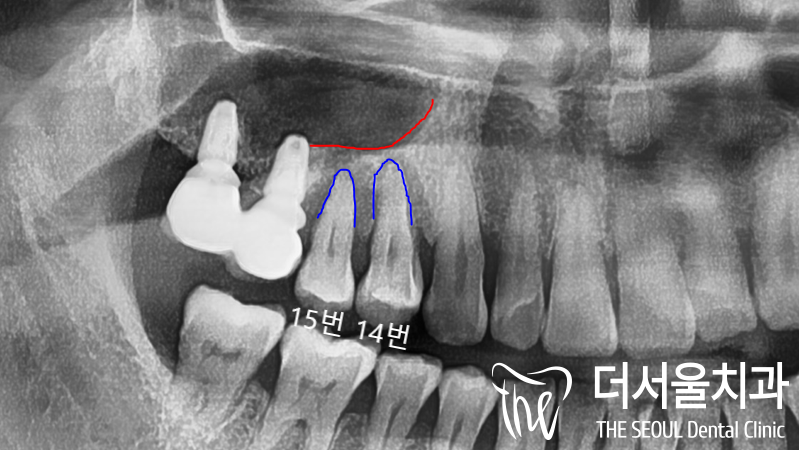

뿌리쪽을 들여다 봤을 때

어둡게 보여지는 ‘염증’ 들도 관찰되었죠.

이런 병소들이 점점 퍼져나가면서

뼈를 녹여서 두께가 얇아진 것입니다.

그럼 시간이 흘러 염증들이

점점 가득차게 되면서

더 큰 수술로 이어질 가능성이 높기에

이렇게 뼈가 얇을 때에는

‘Sinus lifting & GBR’은 필수입니다.

남아있는 치아들을

발치를 했으며 곧 이어

거상술을 집행했습니다.

뼈와 막이 박리가 된 것을

확인을 한 뒤에 그 속으로

뼈 이식재를 이식해드린 뒤

픽스쳐 2개를 식립했습니다.